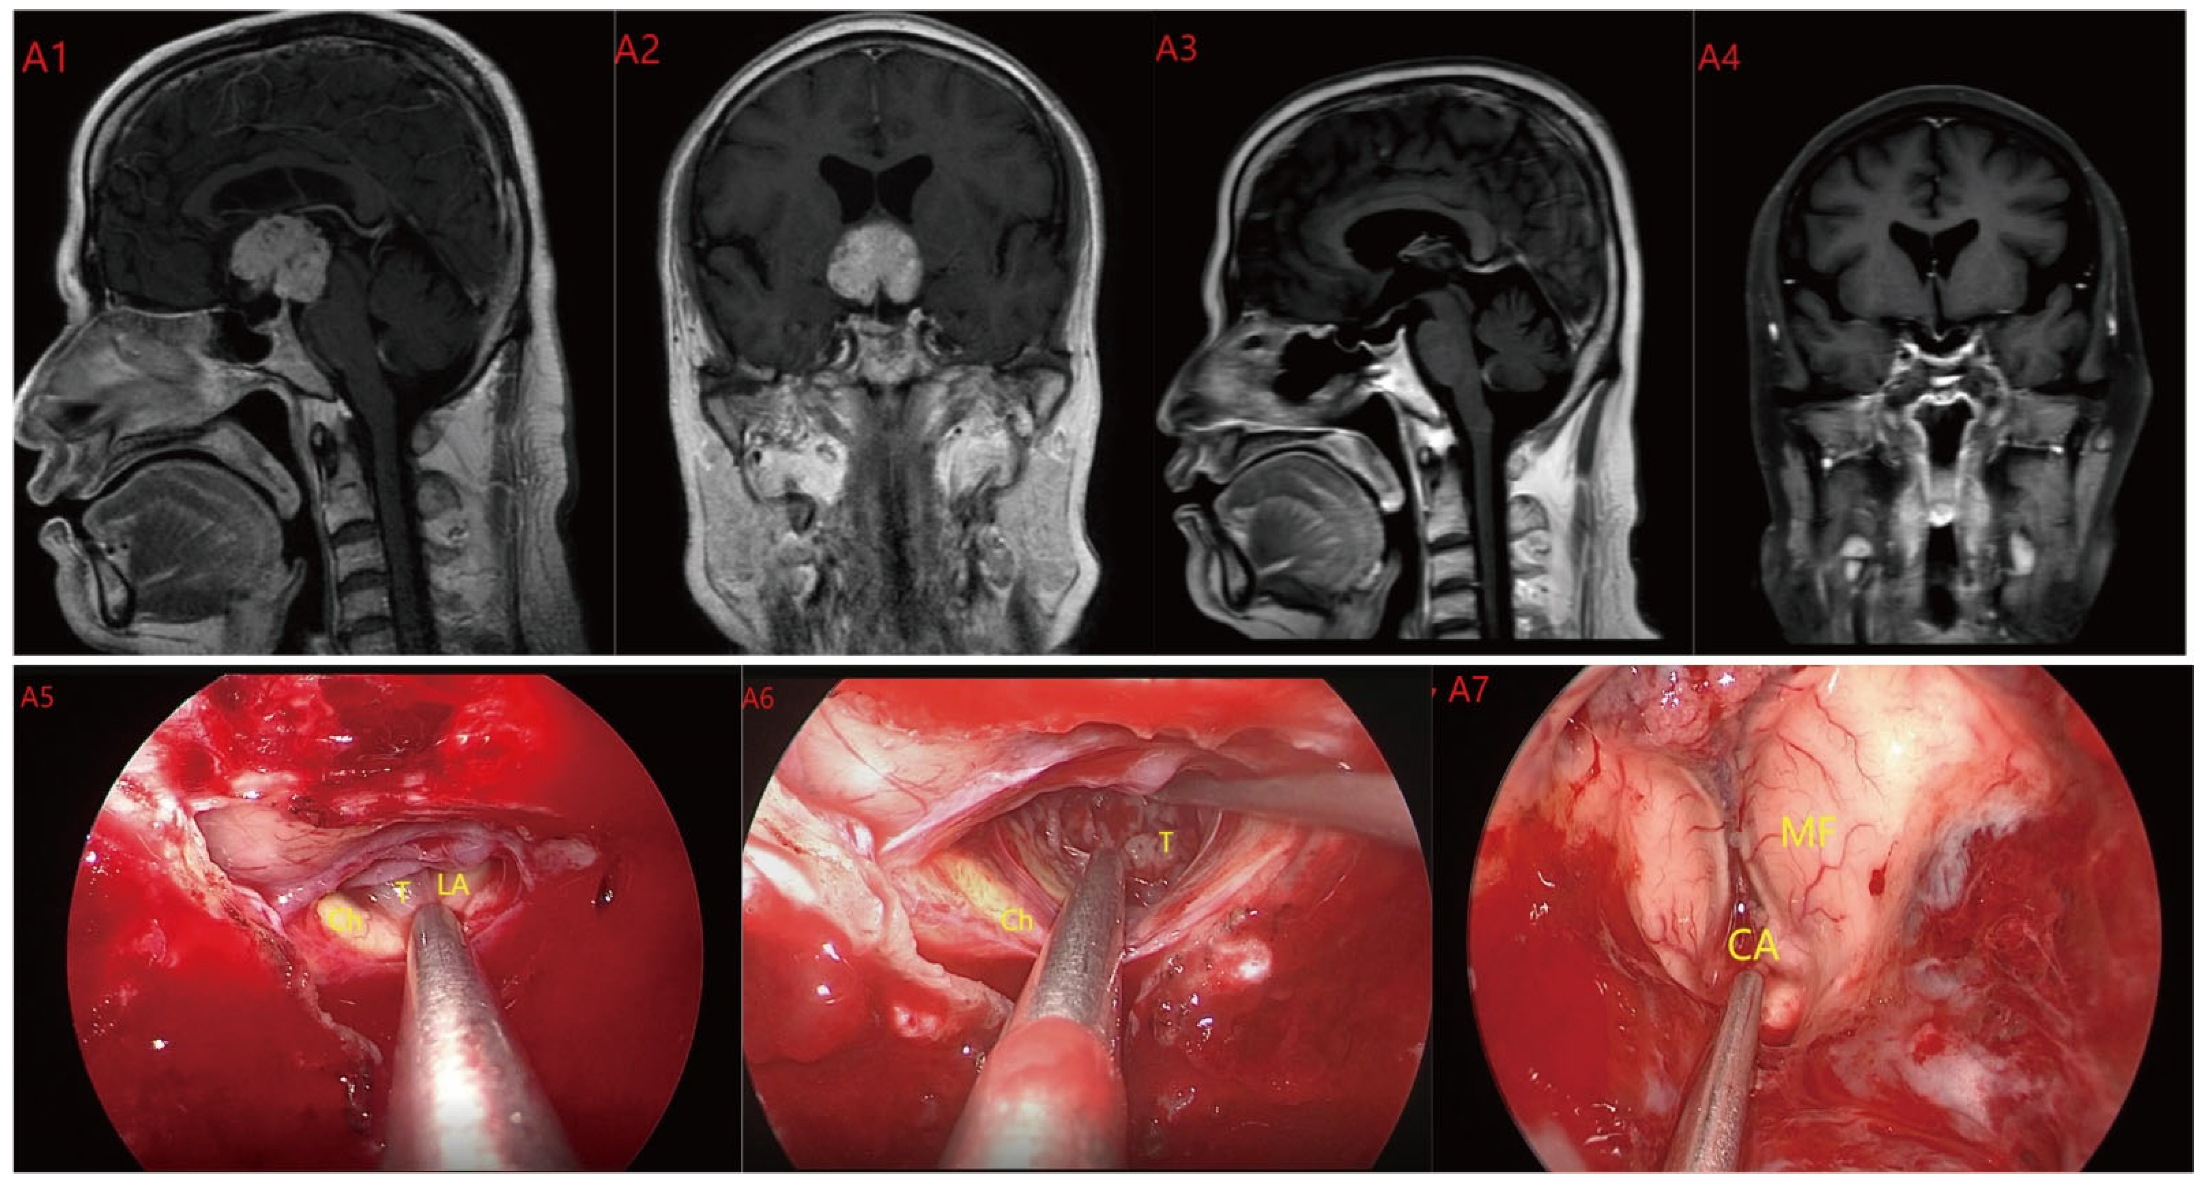

Based on MRI data and intraoperative findings from EEA, we classified PCPs into three types: (1) Type I: Suprasellar/intra-suprasellar (3V floor intact) type: most tumors originate from the segments of the pituitary stalk between diaphragma and infundibulum, as shown in Figure 1. (2) Type II: Suprasellar/intra-suprasellar (3V floor invasive) type: most of the tumors originate from pituitary stalk (PS), or infundibulum and median eminence (ME); the interface between tumor and 3V floor is not clear or has disappeared, and the tumor infiltrates into the bottom of the third ventricle, as shown in Figure 2 and Figure 3. (3) Type III: Intra-third ventricle type; most of the tumors originate from the infundibulum and ME, the tumor grows strictly inside the third ventricle, the 3V floor is intact and covered with arachnoid membrane, as shown in Figure 4 and Figure 5.

Figure 4.

Case 4 Type III: the tumor grows strictly inside the third ventricle. (A1,A2) The TLTA was used; the pituitary stalk could not be seen during the surgery (A5–A7). Finally, the tumor was totally resected (A3,A4). Optic chiasm (Ch), foramen of Monroe (MF), massa intermedia (MI), cerebral aqueduct (CA), tumor (T).